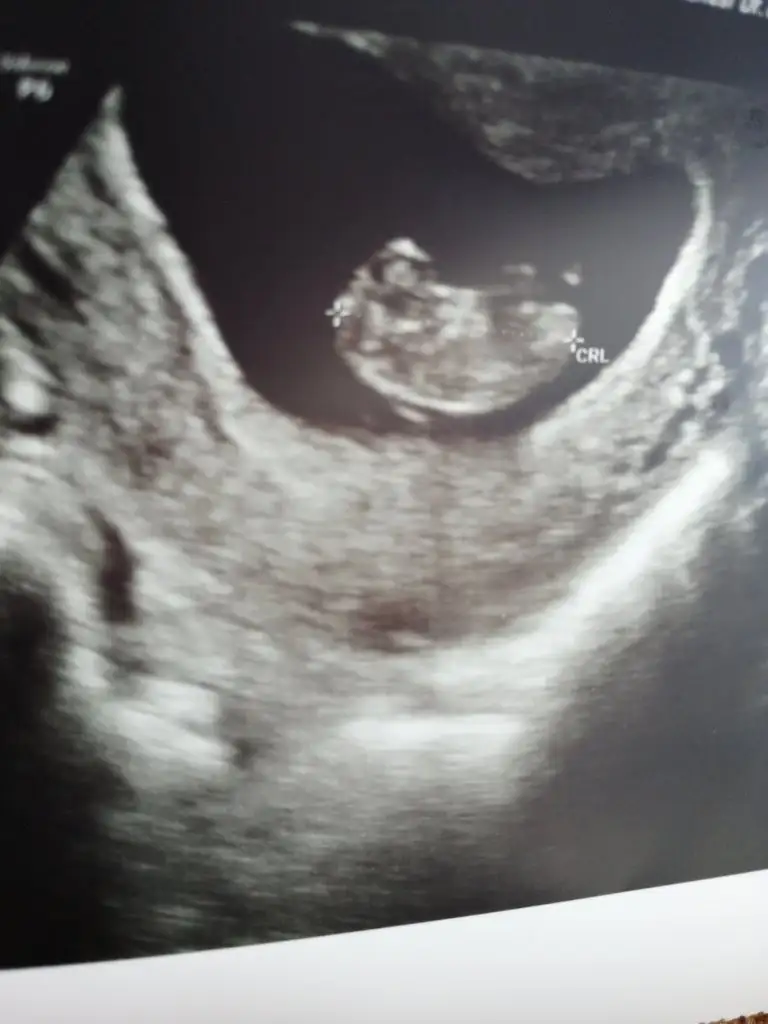

Bende bi tahmin alabilir miyim vajinal kontrol oldum

Eklentiler

• A1AA6C74-3F75-43BF-8C8D-7C62C83CFC95.webp

20,7 KB · Görüntüleme: 105